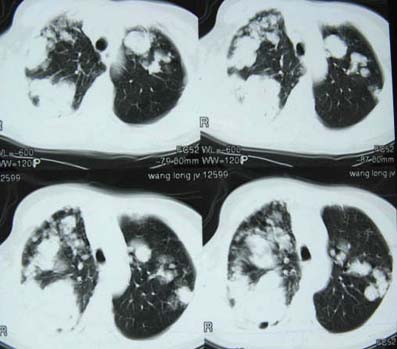

标题: CT8382:男,75,咳嗽,咳血有半年时间。 [打印本页]

标题: CT8382:男,75,咳嗽,咳血有半年时间。

右肺下叶弥漫性片状增高影 纤维组织增生   左肺上叶尖段大结节样增高影边界清楚 中叶下叶大片增高影(内可见钙化)

考虑 双肺继发性肺结核

1.考虑双肺转移,建议增强ct及纤支镜;

2.双肺肺气肿,支扩伴少许感染;

3.双中上肺陈旧性病灶。

1、双肺多发转移瘤可能性大,建议进一步检查。

2、支气管扩张

右上肺后段及左上肺舌段片状影,考虑双肺结核。

双肺弥漫性结节影,考虑双肺转移性肿瘤。